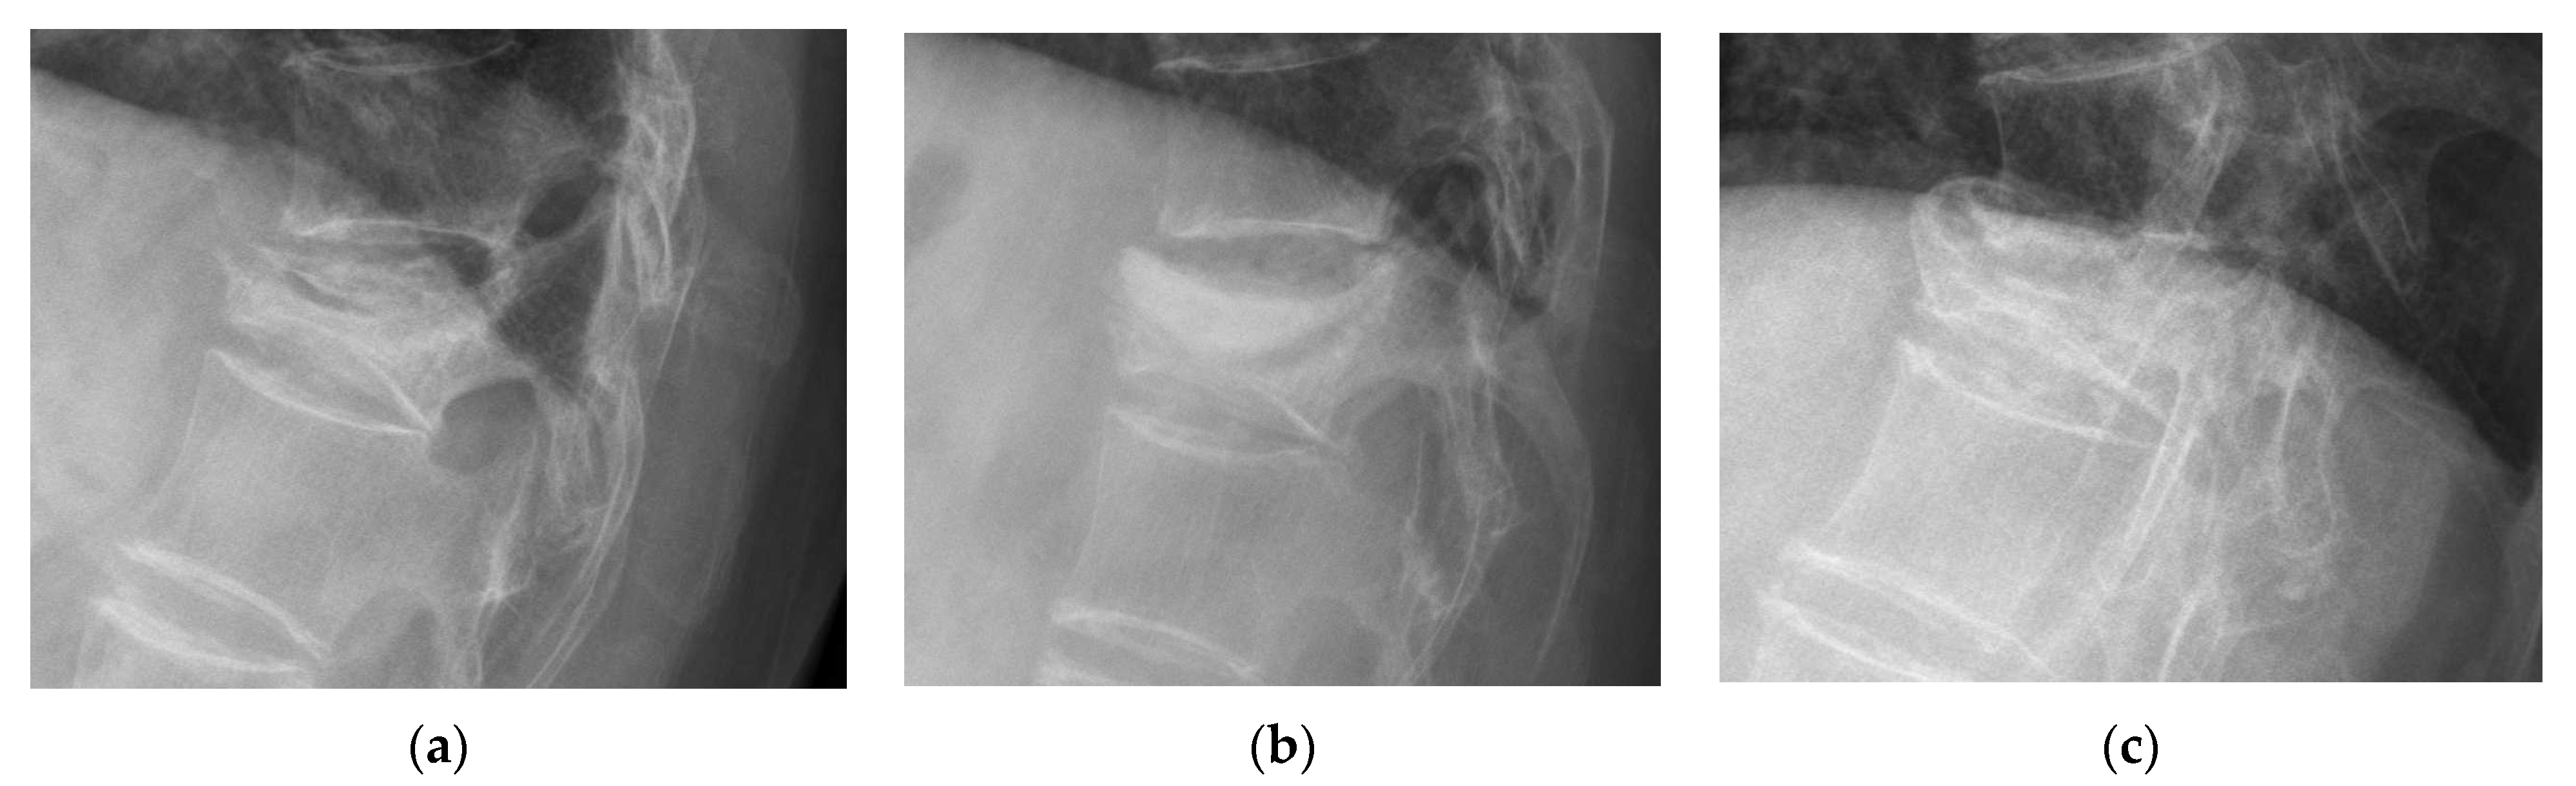

2.2. Measurement of Vertebral Parameters and New Bone Formation